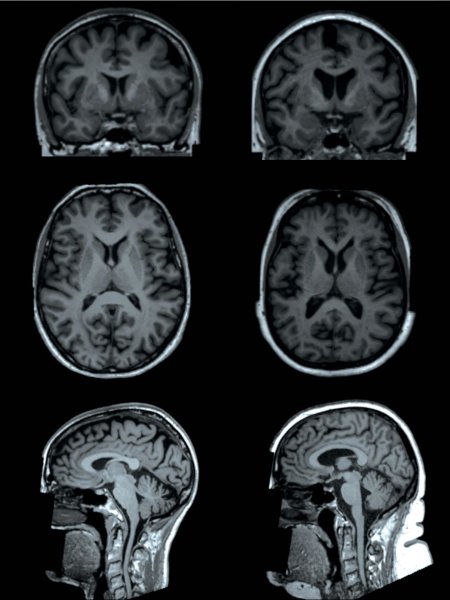

Researchers using sophisticated MRI technology have found that higher levels of body fat are associated with differences in the brain’s form and structure, including smaller volumes of gray matter, according to a new study.

To learn more about these changes, the researchers analyzed brain imaging results from more than 12,000 participants in the UK Biobank study, a major trial begun in 2006 to learn more about the genetic and environmental factors that influence disease. The brain scans used sophisticated MRI techniques that provided information on both the neuron-rich gray matter and the white matter, often referred to as the wiring of the brain.

The results show some clear associations in the patients between body fat percentage and brain form and structure, also known as its morphology.

“We found that having higher levels of fat distributed over the body is associated with smaller volumes of important structures of the brain, including gray matter structures that are located in the center of the brain,” Dr. Dekkers said. “Interestingly, we observed that these associations are different for men and women, suggesting that gender is an important modifier of the link between fat percentage and the size of specific brain structures.”

Analysis showed that, in men, higher total body fat percentage correlated with lower gray matter volume overall and in specific structures involved in the reward circuitry and the movement system. In women, total body fat only showed a significant negative association with the globus pallidus, a structure involved in voluntary movement. For both men and women, higher total body fat percentage increased the likelihood of microscopic changes to the brain’s white matter.